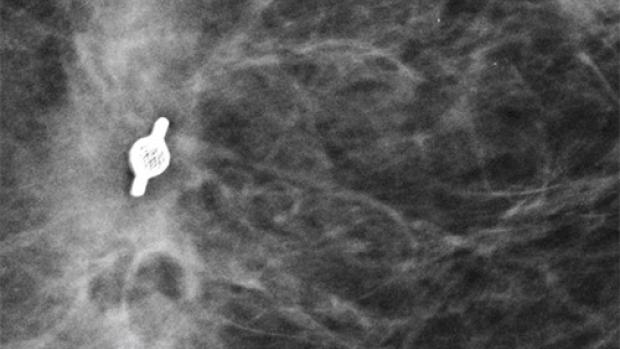

Tumark Professional Q and U markers are sandblasted nitinol, designed to provide outstanding visibility in ultrasound, and excellent visibility under mammography at deployment. In 85% of marker placements, physicians stated the ultrasound visibility was good to excellent upon deployment.2

In the initial data collection study: 91% of markers placed under ultrasound did not migrate, as measured on the post-procedure mammogram.1 In 9 out of 10 cases the marker deployed accurately in ultrasound to the intended area.1